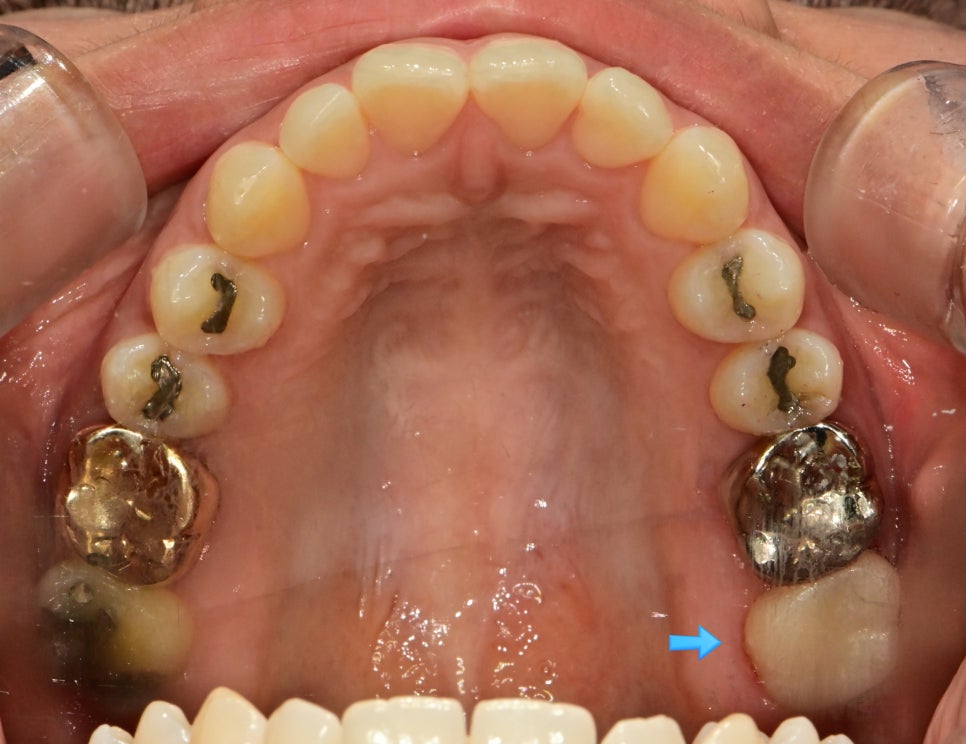

아말감 제거 후 깨끗하게 형성된 와동 임상사진 — 아말감 하방 상태 확인

▲ 아말감 제거 후 드러난 와동 — 아말감 아래 숨어있던 문제를 확인합니다

와동 다른 각도 임상사진 — 인접면 삭제 및 와동 형성 상태 기록

▲ 다각도에서 기록한 와동 형성 상태

아말감 제거 후 드러난 치아 내부 — 한글 주석으로 치아 금(crack)과 충치 부위 표시

▲ 아말감 제거 후 선명하게 드러난 이차 충치와 치아 크랙 — 인레이보다 크라운이 적합한 증례